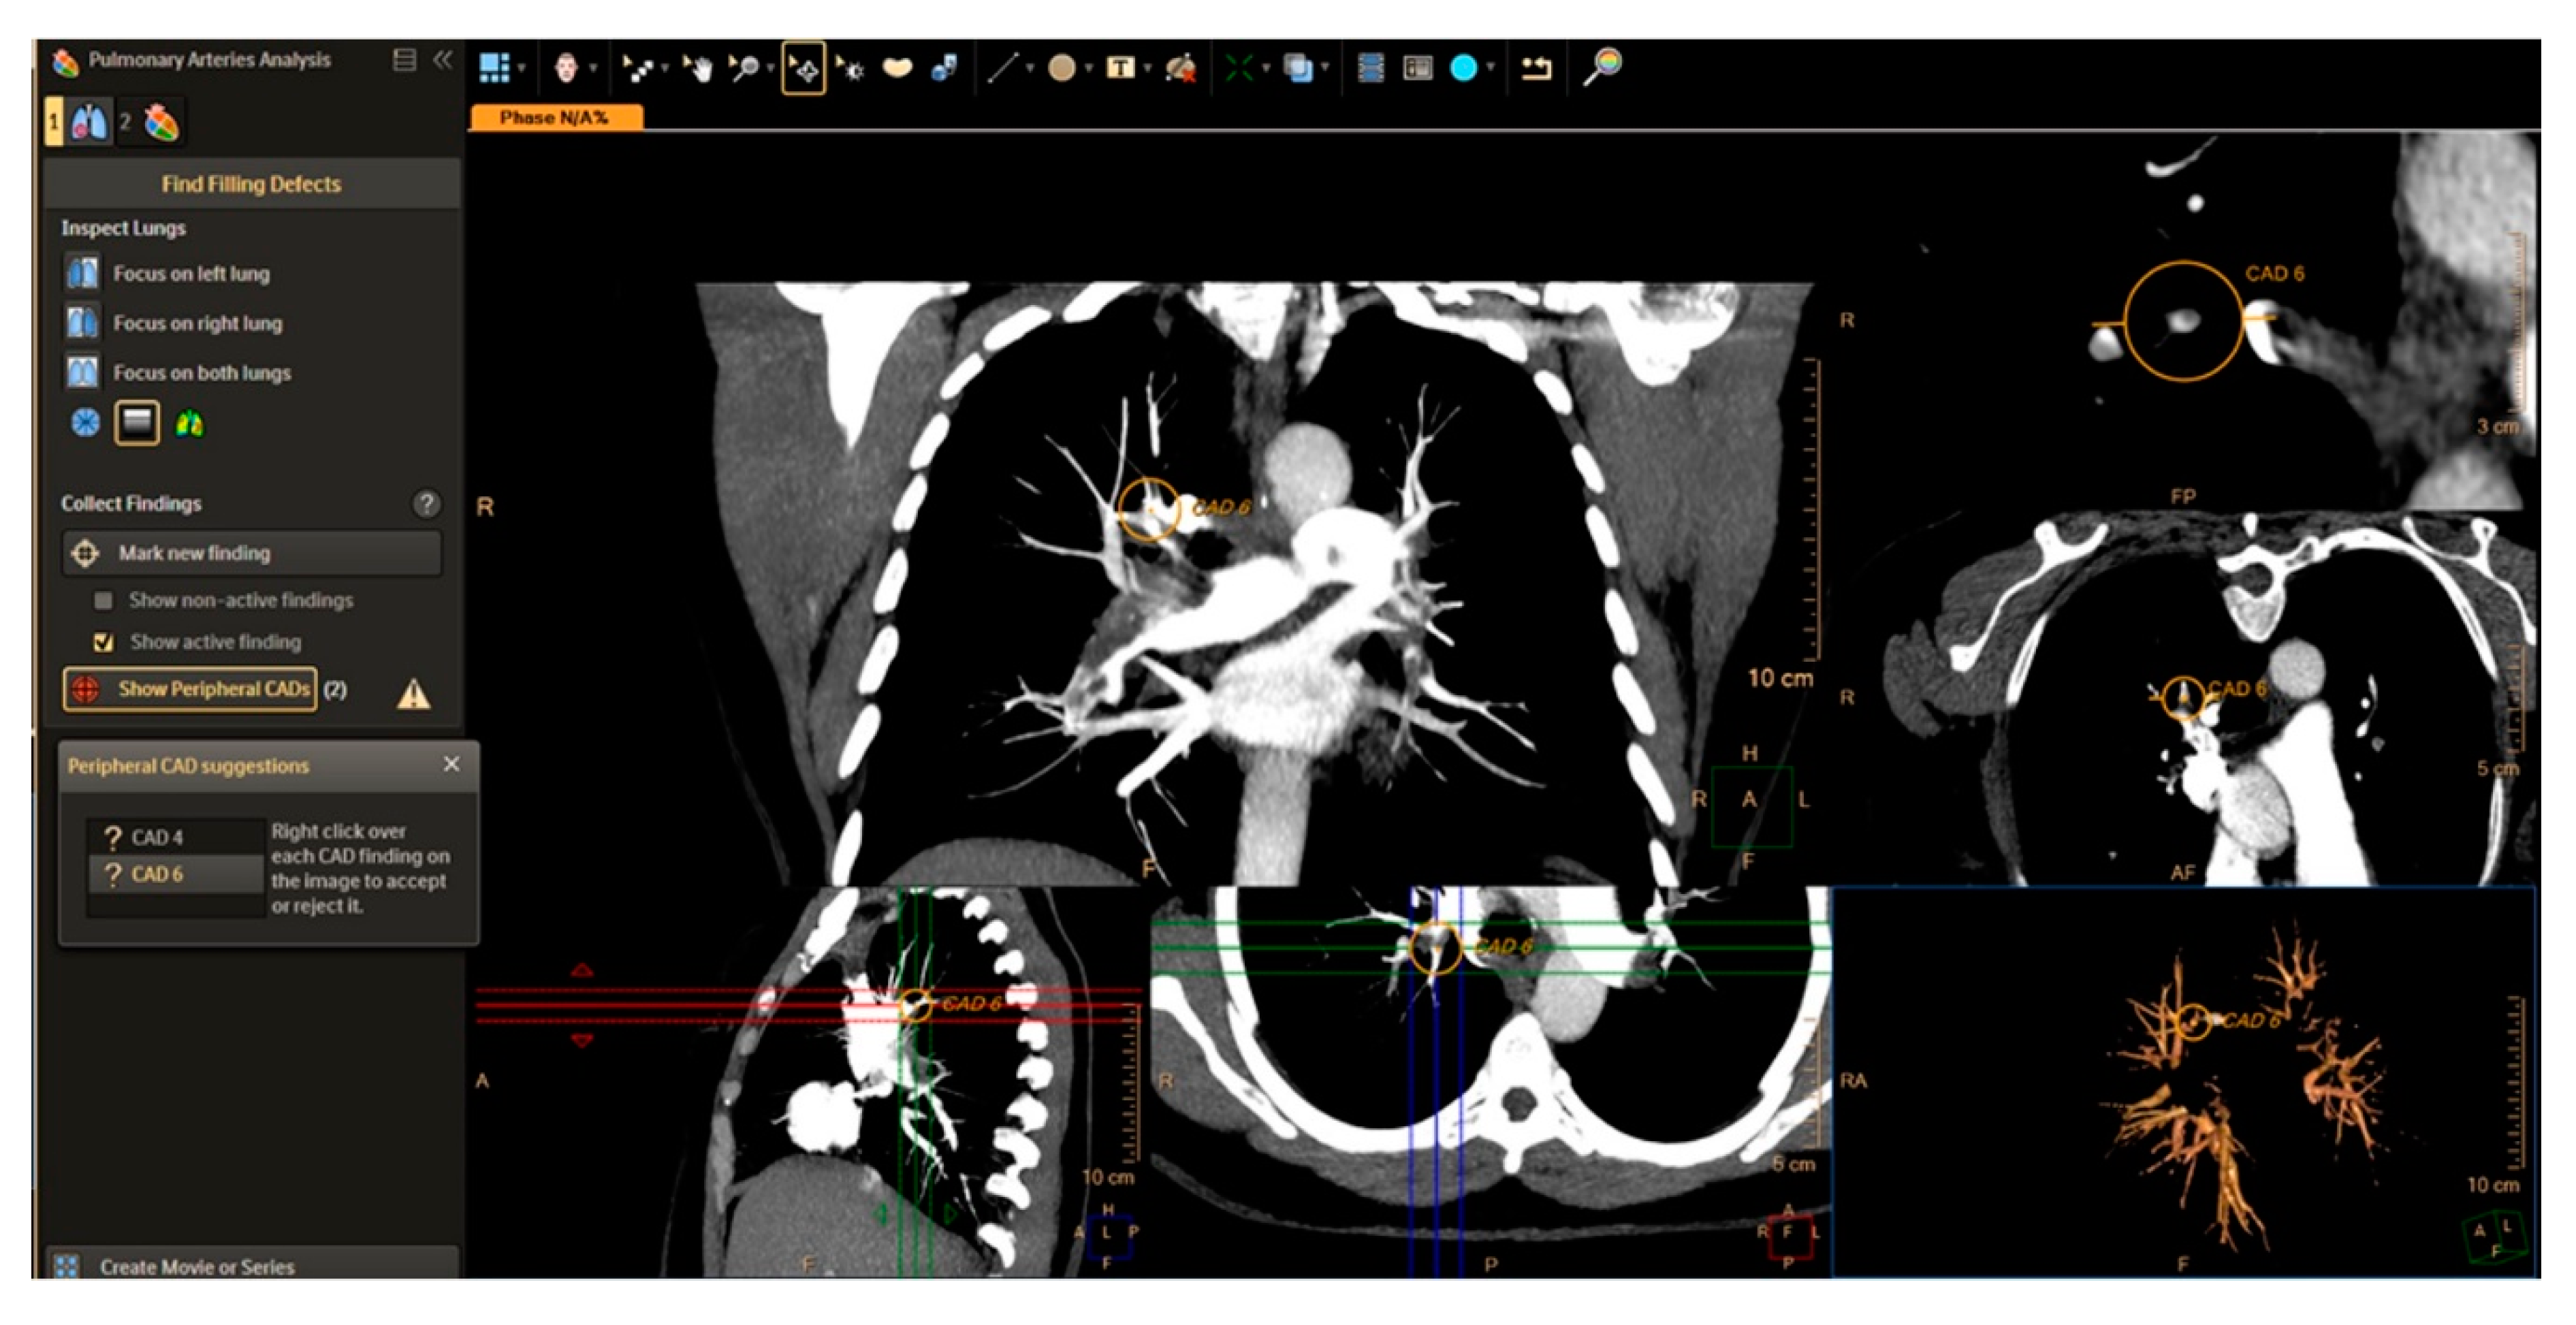

5.1. Computed Tomography Pulmonary Angiography (CTPA)

| CAD | Computed Aided Detection |